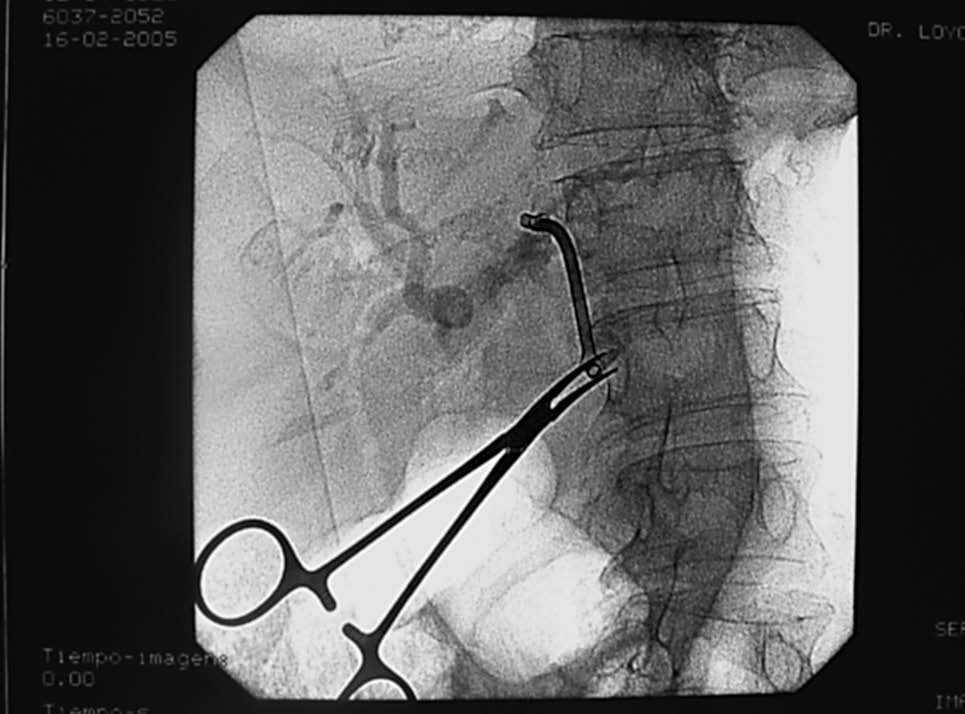

Mujer de 76 años de edad, con antecedentes personales de colecistectomía 30 años antes y de esfinterotomía endoscópica hace 10, por coledocolitiasis. Ingresa en nuestro servicio por presentar colestasis. Los datos analíticos más relevantes son: bilirrubina total 3 mg/dl (0-1,1), GGTP 892 U/l (8-61), fosfatasa alcalina 530 U/l (40-129), GOT 94 U/l (6-38) y GPT 62 U/l (6-41). Se realizan ecografía abdominal y colangio-RM que ponen de manifiesto la presencia de dilatación de las vías biliares y estenosis de la coledocoduodenostomía previa. Ante estos hallazgos, se coloca una prótesis biliar y se realiza drenaje interno-externo. Esta técnica se lleva a cabo en colaboración con el radiólogo intervencionista. En primer lugar, por vía transparietal-hepática se introduce una guía metálica hasta la ampolla de Vater. El endoscopista por vía duodenal sitúa una prótesis de plástico de 10 F y 7 cm, comprobando al terminar el buen anclaje de la misma (fig. 1). Tres días después del procedimiento la paciente refiere dolor abdominal y naúseas, por lo que se solicita nueva ecografía abdominal que demuestra que la prótesis está en el conducto hepático izquierdo. El intento de extracción mediante CPRE resulta infructuoso, por lo que finalmente la prótesis se recupera por vía transparietal-hepática (fig. 2).

Fig. 1. Colocación de endoprótesis biliar por aproximación conjunta transparietal-hepática y duodenal.